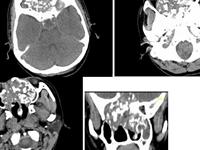

相关图片